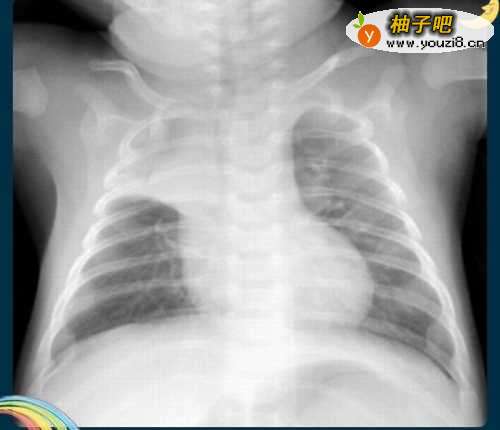

3哎,一不小心,感冒居然还成功了。高烧不退,卧床不起。没办法,去医院吧。到医院一检查,恭喜你,已经烧成肺炎。赶快住院吧,再也不可以拖下去了。

4彩超结果出来了,医生一看,大吃一惊。说你如何搞的,病成这样,才到医院里来,以前你在干啥。自己的身体不当回事。肺部的阴影已经快要布满整个肺部了。

5医生告诉家人,已经是肺癌了。可以不可以治好,不好说,尽人事听天命吧。现在那个后悔呀,早知如此,何必当初。